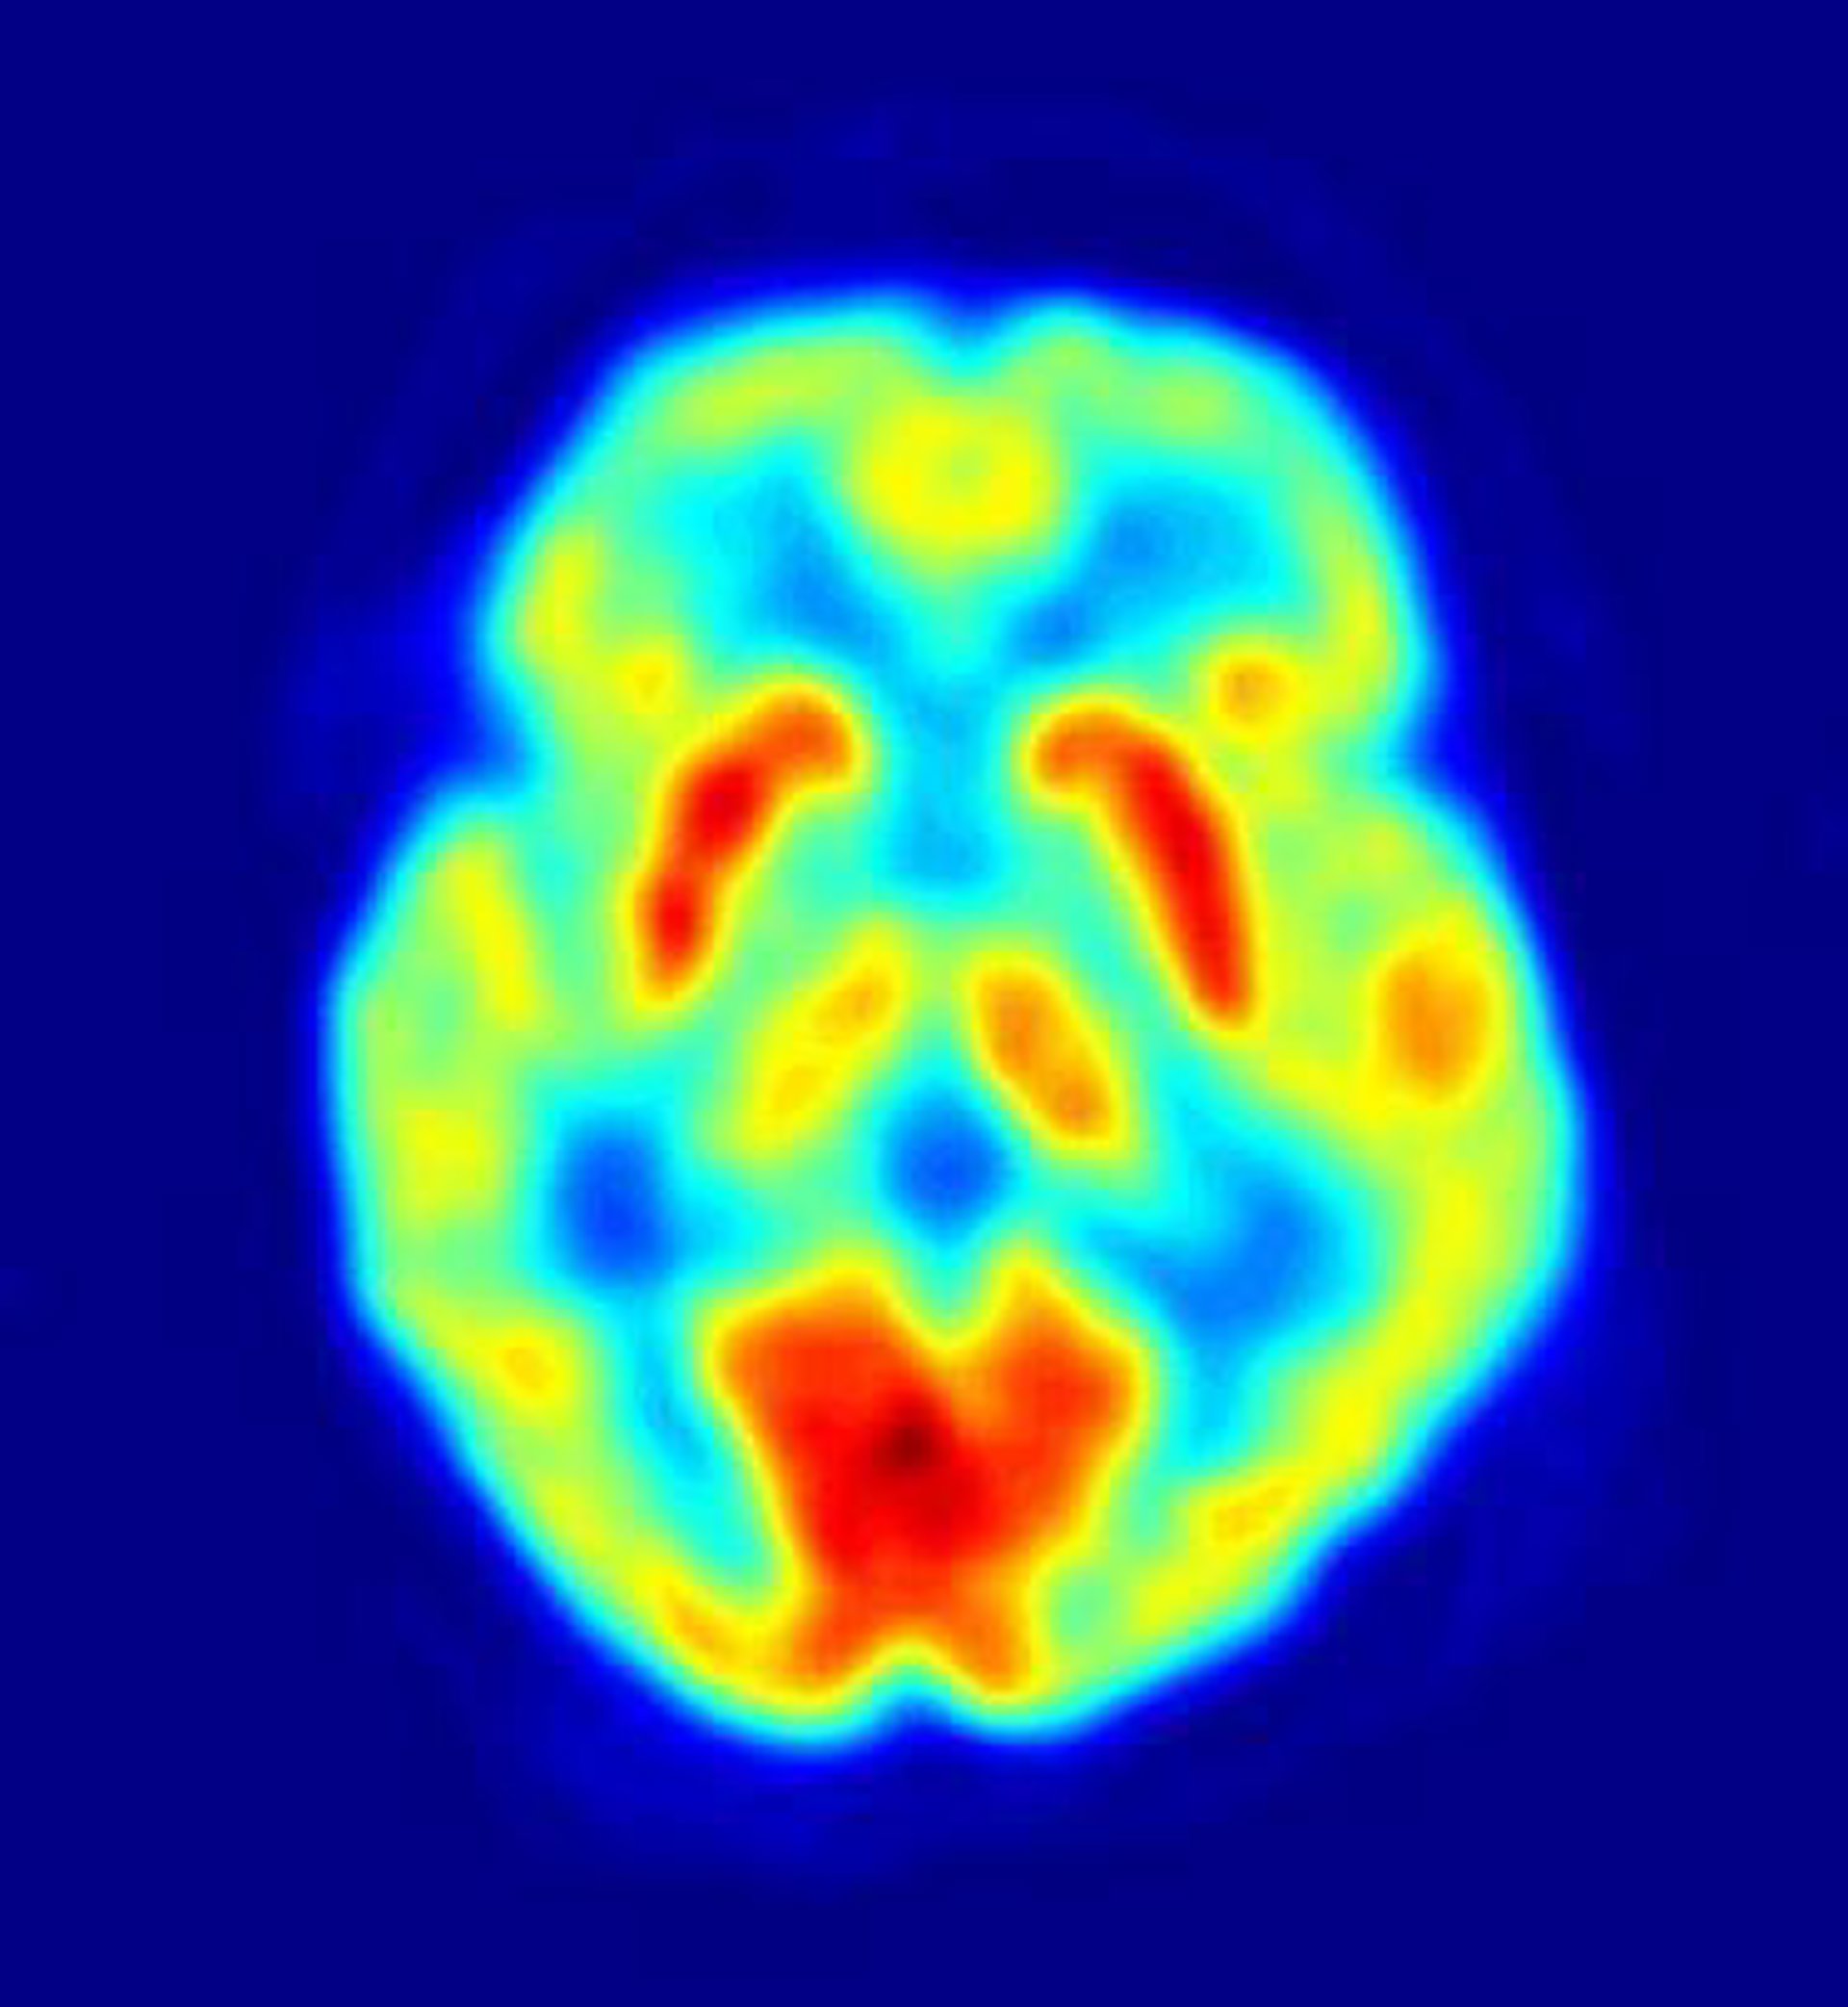

Según explica Cosimo Urgesi, director del trabajo, "los estudios de neuroimagen han vinculado la actividad con una gran red cerebral que conecta las cortezas frontal, parietal y temporal con las experiencias espirituales pero se carece de información sobre el vínculo causal entre tal red y la espiritualidad".

Los investigadores combinaron análisis de puntuaciones de AT obtenidas de pacientes de tumor cerebral antes y después de haber sido operados para extirpar su tumor, con técnicas avanzadas para analizar la localización exacta de las lesiones cerebrales tras la cirugía.

El grupo descubrió que el daño selectivo en las regiones parietales izquierda y derecha posterior inducía un aumento específico en AT. "Nuestro estudio de análisis de síntomas-lesiones es la primera demostración de un vínculo causativo entre el funcionamiento cerebral y la AT", afirma Urgesi.

El investigador explica que los daños en las áreas parietal posterior inducían cambios muy rápidos de una dimensión de la personalidad estable asociada con la conciencia auto-referencial transcendental. Por ello, la actividad neural parietal anómala podría estar en la base de actitudes y conductas espirituales y religiosas.